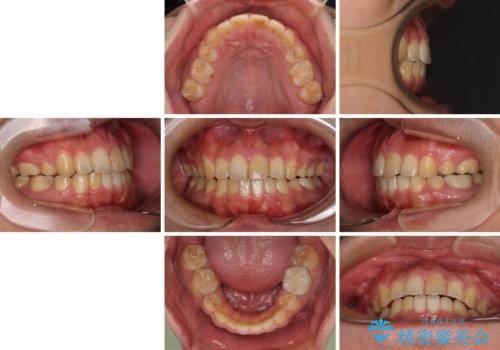

後戻りでデコボコの前歯 インビザライン矯正治療

- 高校時代に行った抜歯矯正が後戻りをしたとのことで来院された患者様です。

再矯正であることから、目立ちにくい装置を希望されたため、インビザラインにて矯正治療を行うこととしました。

下顎骨が左側に変位しているため、正中が合わないことは予想できましたが、歯列が整った後も咬み合わせが安定せず、咬み合わせを落ち着かせるために1年以上の期間を要しました。